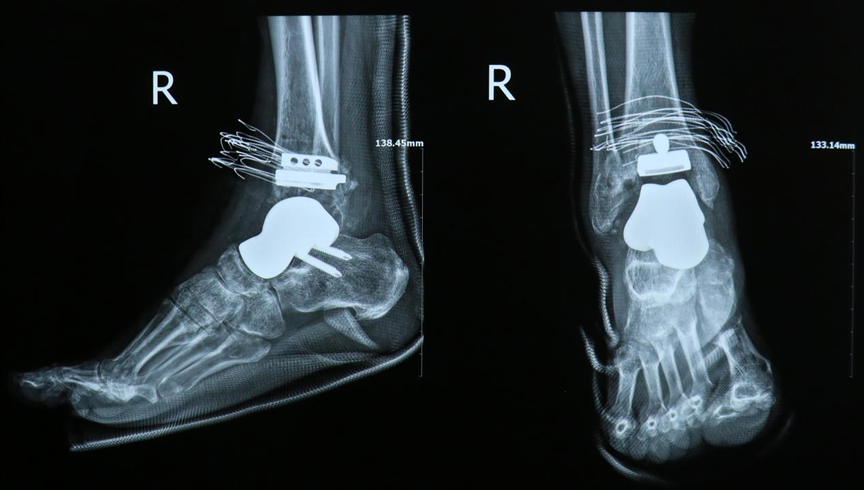

孙先生术后x光片

手术过程中,医疗团队严格按照术前通过 3D 模具设计的截骨路径,精准置入截骨导板,依次完成精准截骨、力线纠正及假体安放等关键操作。整个手术流程规范有序,进展十分顺利。术后检查显示,定制假体位置精准,关节力线恢复良好,孙先生对治疗效果反馈满意,术后恢复情况理想。